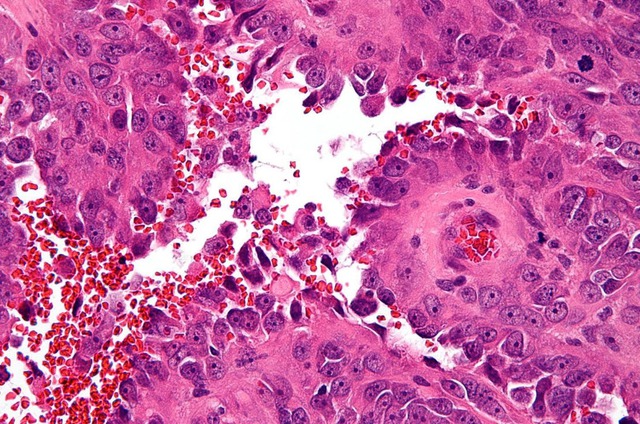

Hình ảnh mô bệnh học cho thấy các tế bào nội mô mạch máu tăng sinh bất thường – đặc trưng của ung thư angiosarcoma.

Sinh thiết là bắt buộc. Các dấu hiệu mô học như tế bào nội mô bất thường, thành mạch bất thường, thể hiện sự tăng sinh mao mạch, nhân dị dạng, nhiều phân bào. Miễn dịch học (ví dụ CD31, ERG, CD34) giúp xác nhận nguồn gốc nội mô. Loại bỏ các dạng giả như u mạch lành, u mạch máu nhỏ, các tổn thương mạch máu phản ứng.